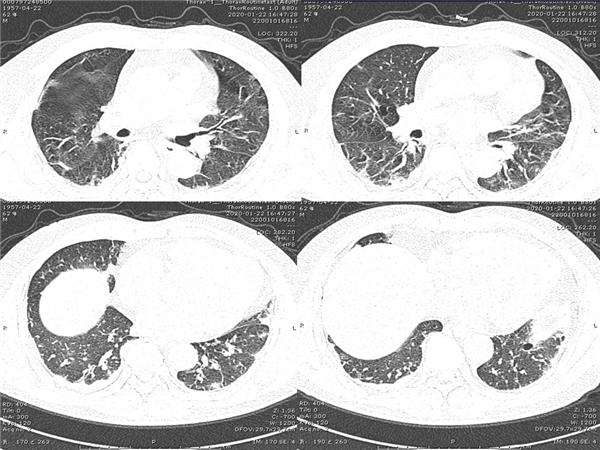

【病例分享】新型冠狀病毒感染肺部CT影像4例(常德市第一人民醫(yī)院)